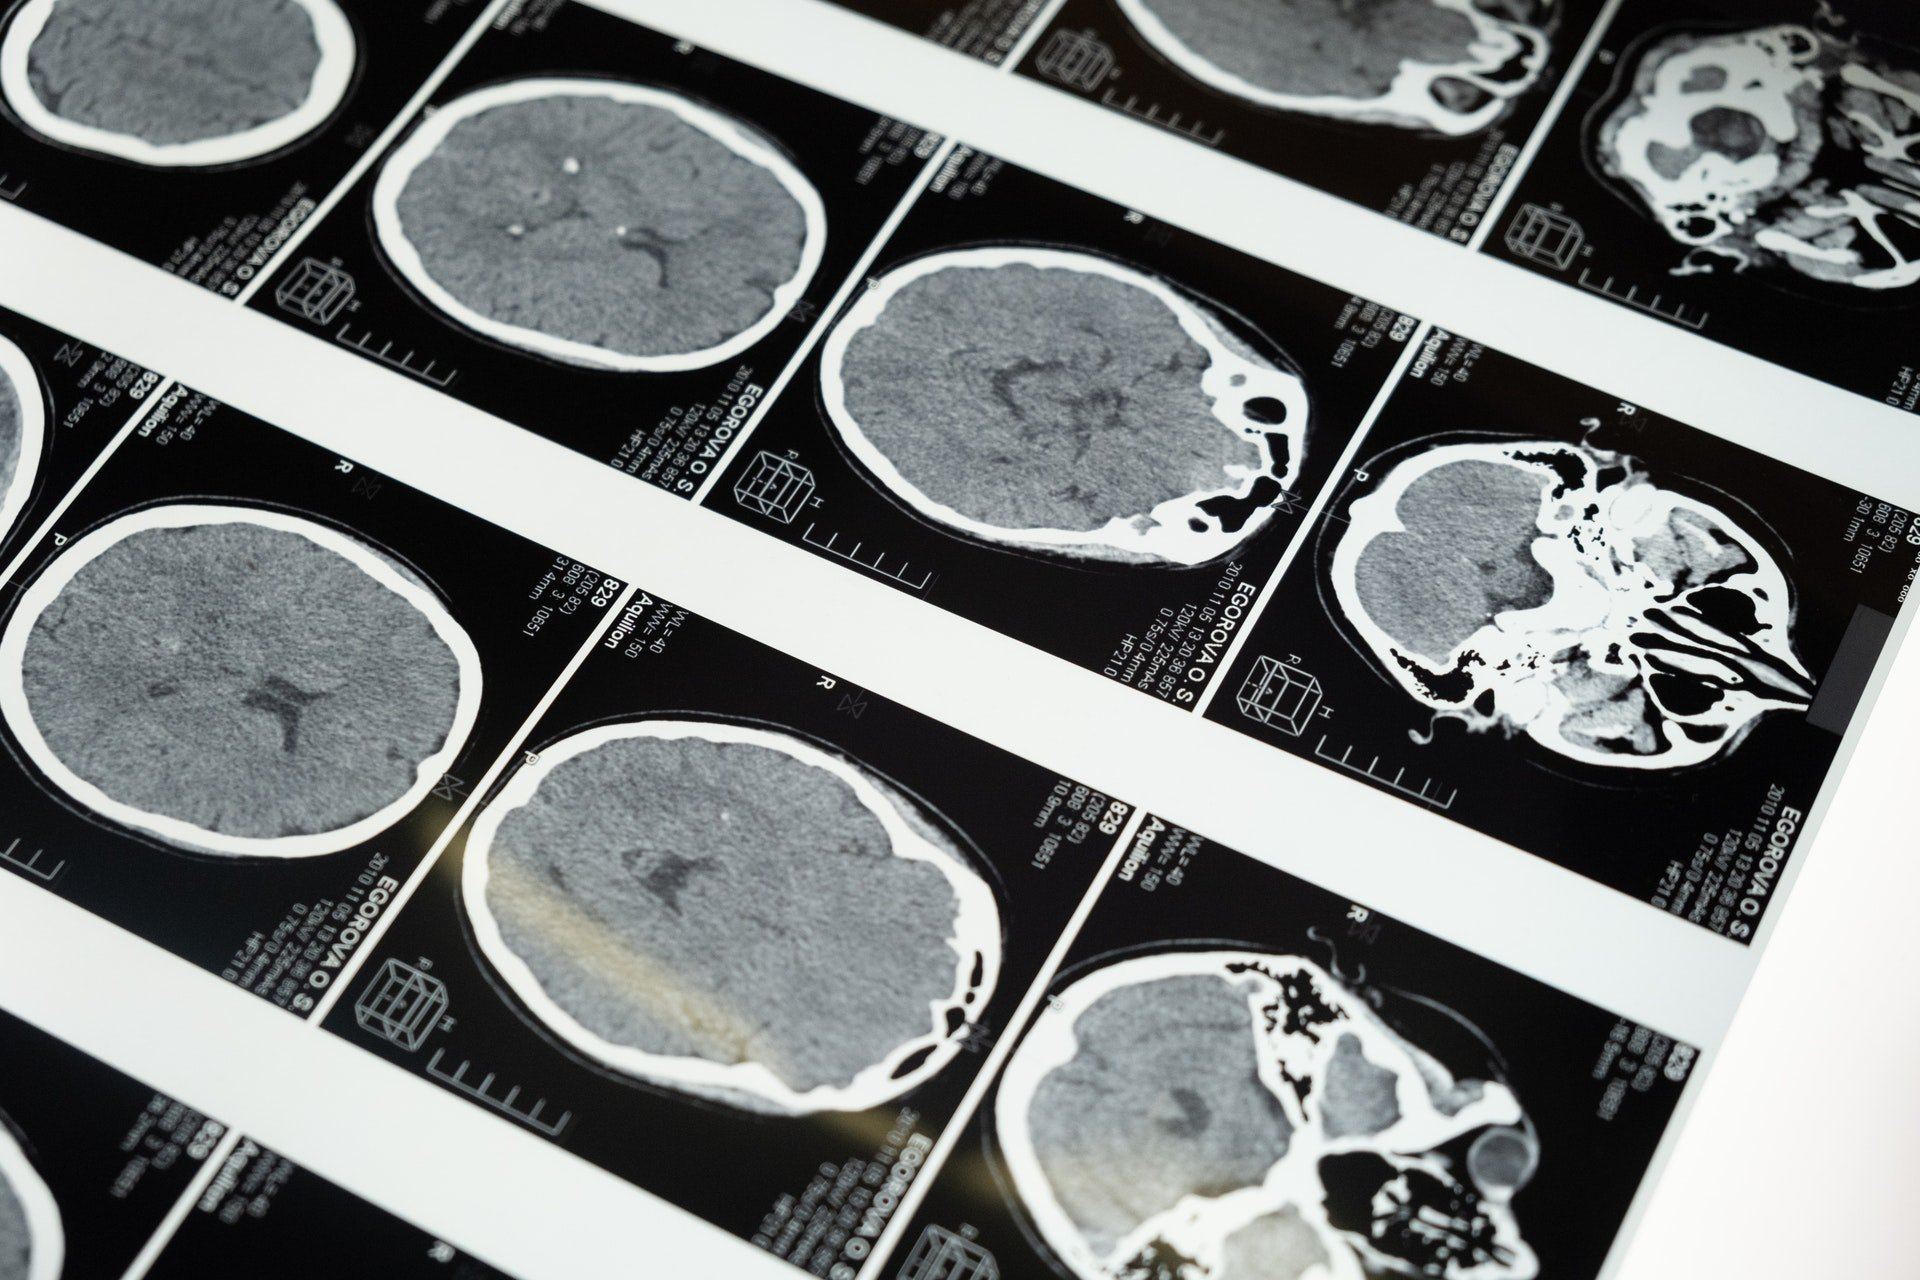

Внутри мозга: 5 заблуждений, опровергнутых наукой

Человеческий мозг – одна из самых загадочных структур, окруженная множеством мифов. Кажется, что проще разгадать тайны космоса, чем до конца понять, что происходит в черепной коробке у человека. Но на некоторые вопросы все же находятся ответы, которые меняют наше представление о работе мозга. Эксперты социального проекта МЕМИНИ, запустившего совместно с отрядом «ЛизаАлерт» вторую волну образовательной кампании #ДеменцияНеСтарость, помогают разобраться в распространенных заблуждениях, которые пора оставить в прошлом.